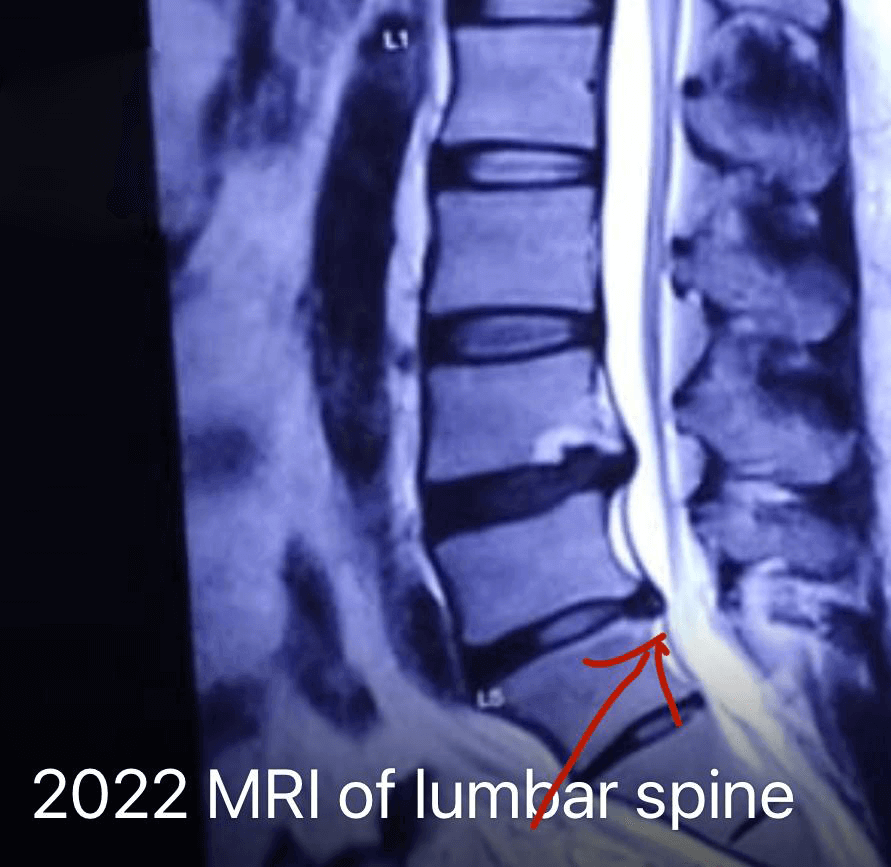

The 2022 MRI shows a marked reduction in the L4–L5 disc protrusion following minimally invasive disc nucleolysis and targeted nerve root injections. Neural decompression is clearly visible, with restoration of normal epidural space and decreased inflammation, correlating with the patient’s complete recovery and return to daily activities without pain.

This case demonstrates the effectiveness of IBAP Clinic’s advanced non-surgical spine interventions in treating lumbar disc prolapse with radiculopathy. Early diagnosis, precise imaging, and targeted procedures—including lumbar epidural injections, disc nucleolysis, facet injections, and nerve blocks—resulted in complete symptom resolution. The patient achieved full functional recovery, with follow-up MRI confirming substantial disc regression and nerve decompression. This highlights IBAP’s commitment to restoring mobility, preventing neurological decline, and delivering long-term relief without surgery.